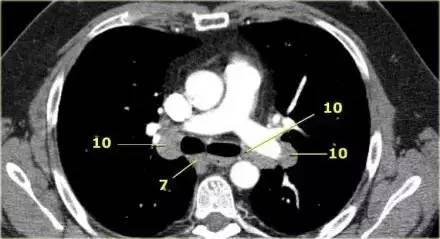

肺 CT 横断面上的隆突下淋巴结(7)、肺门淋巴结(10)